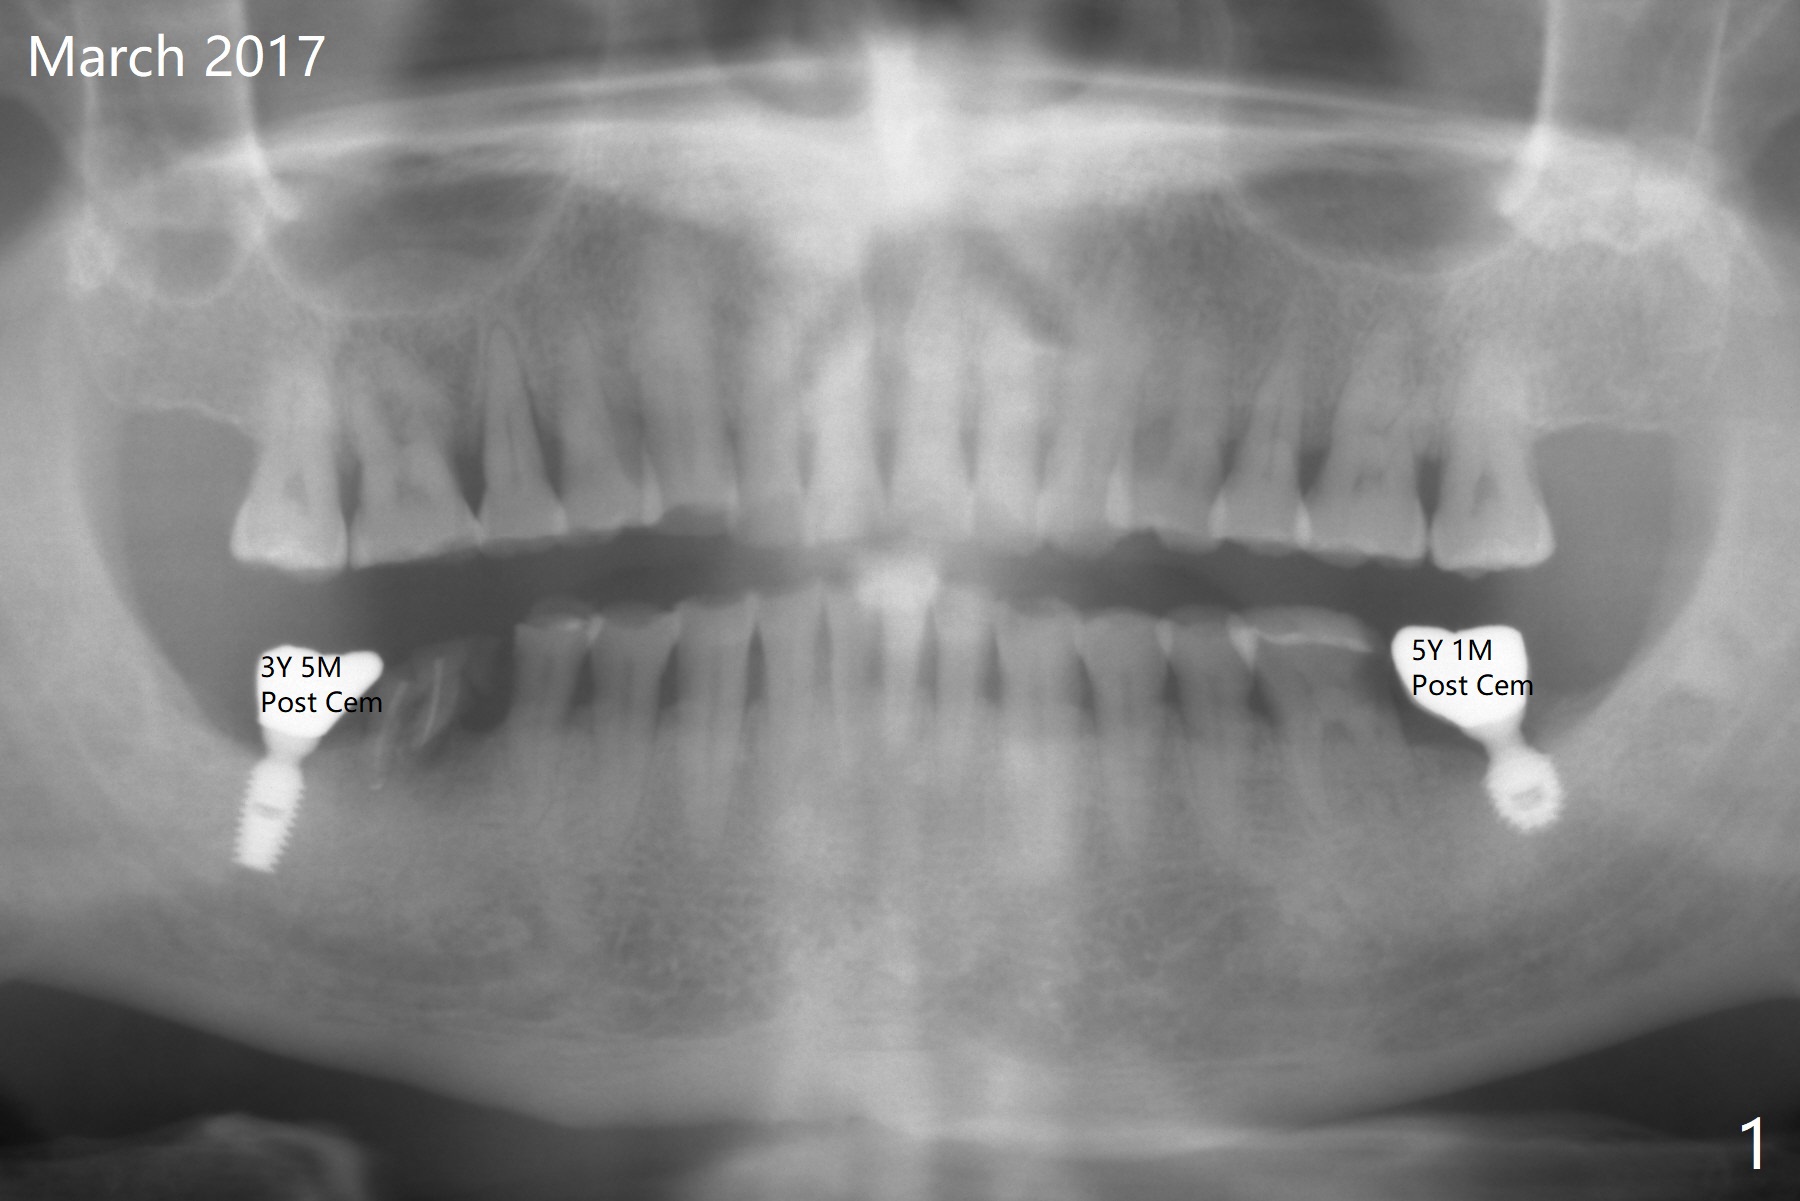

A 60-year-old man is a bruxer with severe occlusal wear (Fig.1-4). He requests implant to replace residual roots at #30 (Fig.4). A 5x11.5 mm implant will be placed. The abutment length should be limited because of limited crown height. An immediate provisional should be as low as possible.